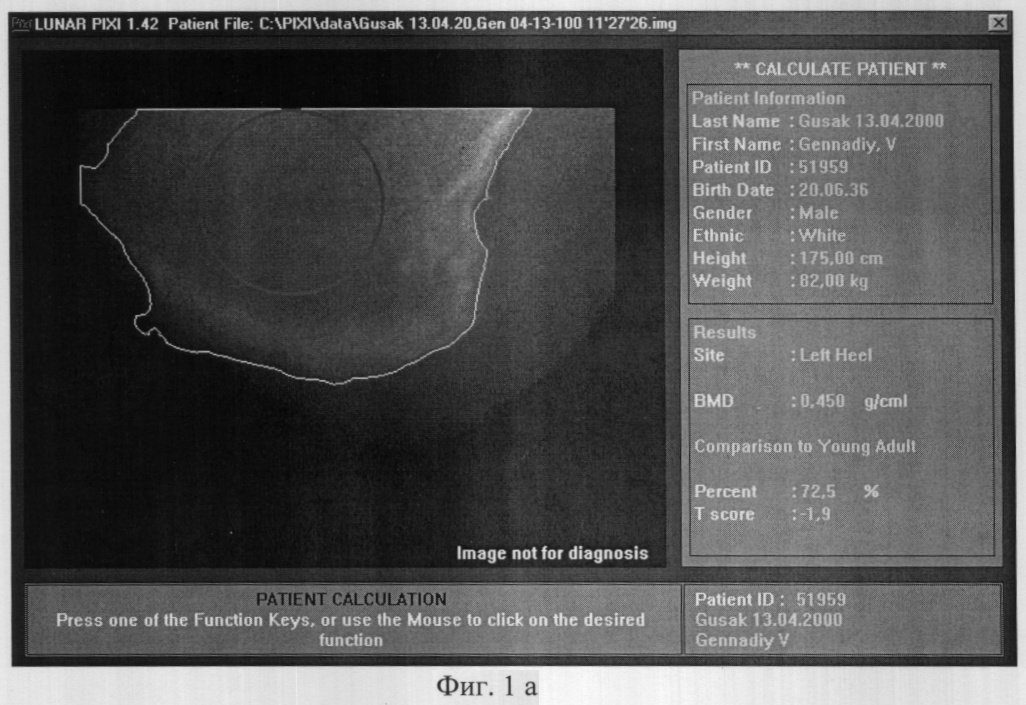

До операции 28.10.1999 года больному проведено исследование минеральной плотности костной ткани (МПКТ) правой пяточной кости, на денситометре фирмы LUNAR (США) и 25.10.1999 года показателя реографического индекса (РИ) правой голени, на реографе “РИСТА-131-РЕО” (г.Таганрог). Выявили следующие данные:

– МПКТ правой пяточной кости – 0,250 г/см2 (см. фиг.2а);

– РИ правой голени – 0.016 Ом (см. фиг.2 b).

Прогноз сращения перелома неблагоприятный – более 6-ти месяцев, т.к. МПКТ ниже 0.300 г/см2, а РИ ниже 0.02 Ом.